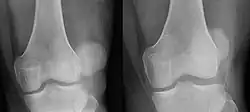

Zwichnięcie rzepki – przemieszczenie rzepki, w którym wypada ona z bruzdy międzykłykciowej. Najczęściej rzepka ulega zwichnięciu do boku.